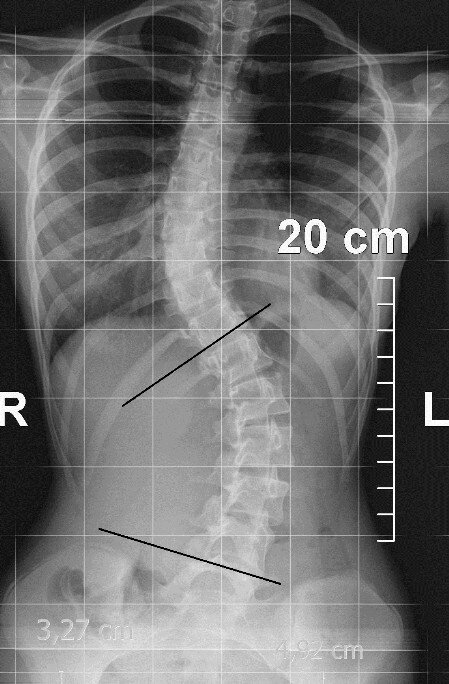

Valutazione della scoliosi

La scoliosi è una deformità tridimensionale: valutiamo curva, rotazione, compensi e respirazione. Quando utile, integriamo la lettura degli esami disponibili.